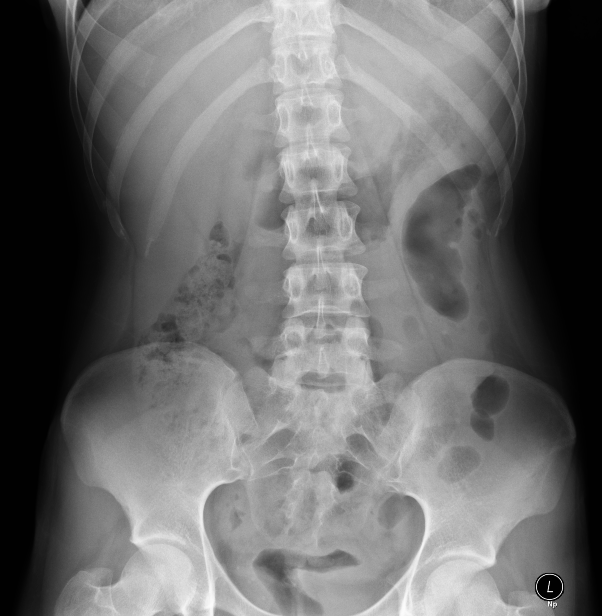

| 8 |

Normal |

Correct |